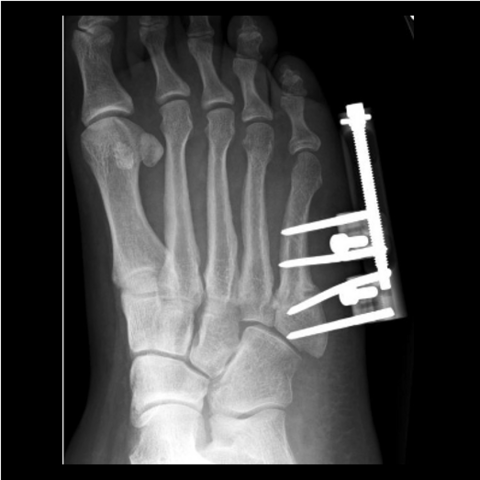

Figure 5b

Figure 5b. The 24-year-old required hardware removal and application of external fixation for gradual compression. Most cases heal within 6 weeks with gradual compression weekly.